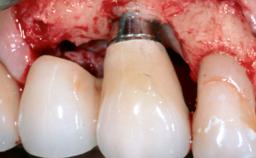

Ridge Preservation and Implant Placement for a Fixed Dental Prosthesis After a Car Accident

# of Implants 4

Type of Implants One-Piece|Reduced-Diameter

Bone Augmentation Horizontal|Simultaneous|Sinus Floor Elevation|Staged

Augmentation Materials Xenogenous|Membrane